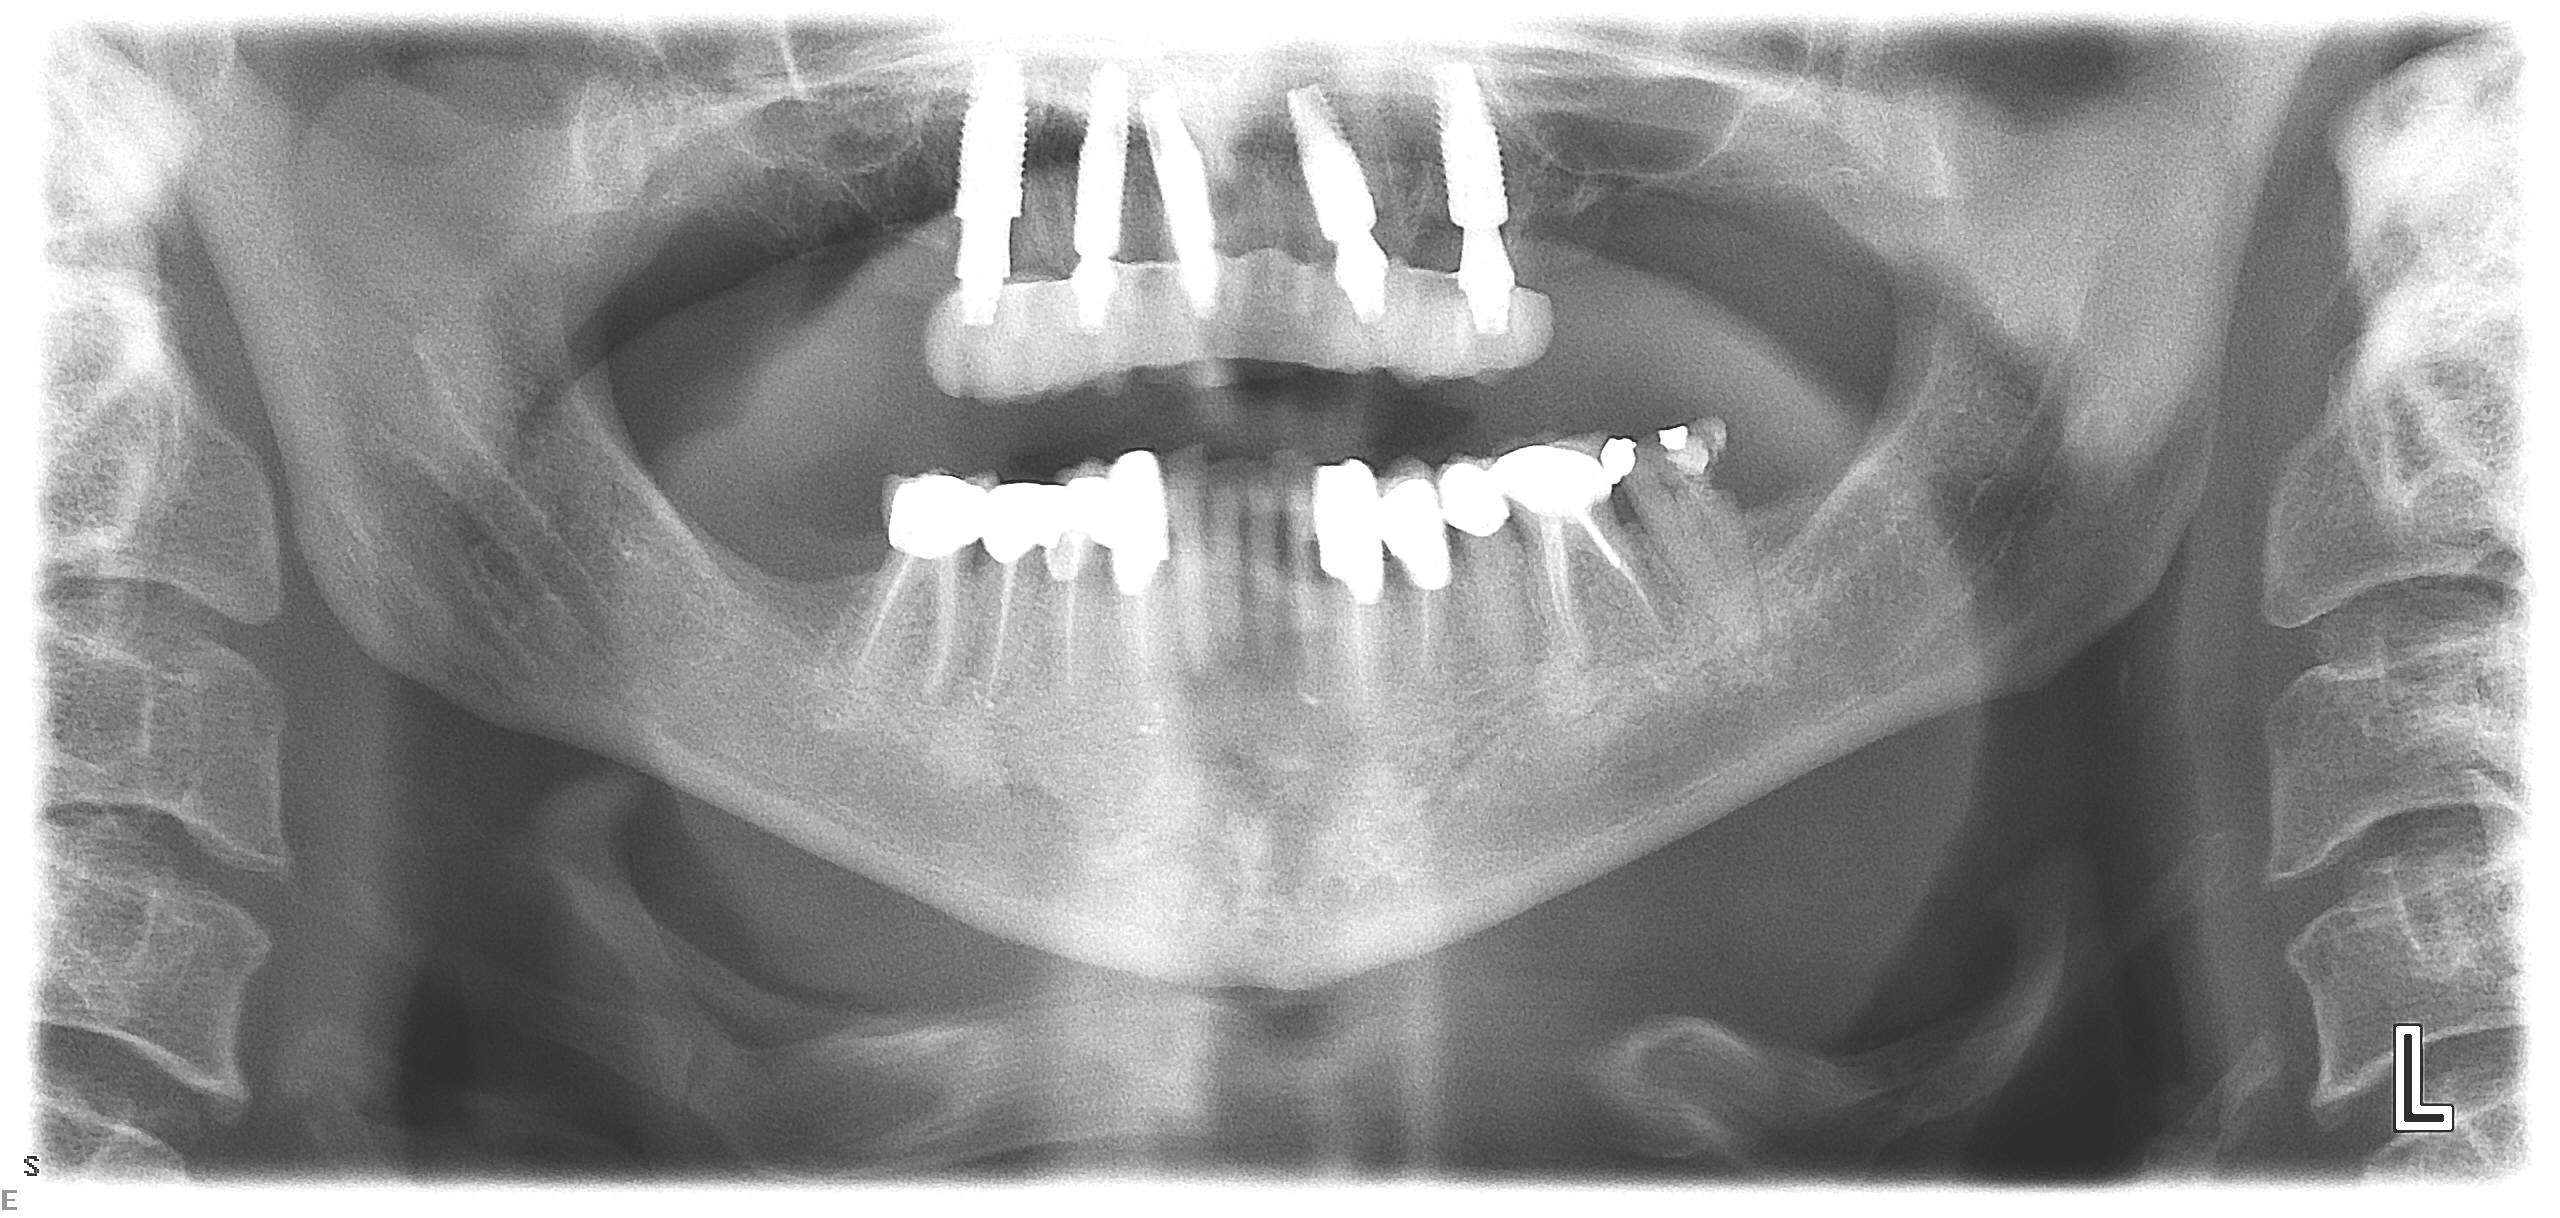

Fig 11. Initial panoramic radiograph.

Figure 11

At the initial visit, a panoramic x-ray (Figure 11) and periapical x-rays were taken. The patient was photographed to capture her full face and shoulders, and a digital scan of the maxillary dentition was obtained. This file was electronically sent to the implant company to complete the VSD.